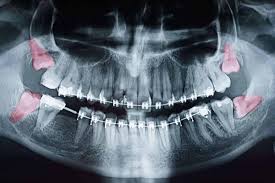

Von der Wuchsrichtung des Zahnes davon wie viel von dem jeweiligen Zahn bereits im Kiefer angelegt und verwachsen war und. Verläuft der Durchbruch der Weisheitszähne bei einigen Menschen ohne Komplikationen so leiden andere unter starken Schmerzen und Entzündungen die sich über mehrere Monate hinweg ziehen. Schmerzen nach dem Ziehen der Weisheitszähne.

Wie stark die Schmerzen sind und wie lange sie andauern hängt von einigen Faktoren ab. Dann allerdings sollten diese langsam abklingen. Bei den meisten Entfernungen der Weisheitszähne entstehen nur leichte Schmerzen oft hat man überhaupt keine.

Es dauert je nach der Größe des Weisheitszahns und sonstigen Faktoren recht lange bis die Wunde vollständig verheilt ist. Das durchschnittliche Alter in dem die Weisheitszähne durchbrechen beträgt etwa 16 Jahre. Es kann 7-14 Tage dauern bis sie vollständig abklingen.

Dann allerdings sollten diese langsam abklingen. Ist das nicht der Fall und verstärken sich die Schmerzen sogar sollte dringend der Zahnarzt aufgesucht werden. Ablauf Ablauf was Sie beachten müssen. Schmerzen nach Weisheitszahn OP wie lange normal. Wie lange dauern die Schmerzen normalerweise an. Es kann 7-14 Tage dauern bis sie vollständig abklingen. Die Fäden zieht der Zahnarzt in der Regel nach 7-10 Tagen. Mit welchem Alter brechen die Weisheitszähne durch. Die Schmerzen nach einer Weisheitszahn OP können 7 bis 14 Tage anhalten allerdings mit abklingender Intensität.

Dies hängt natürlich hauptsächlich von der Schwere des Eingriffs ab. Die Schmerzen können jedoch schon unmittelbar nach einigen Stunden nach dem Eingriff abklingen. Auch am nächsten Tag muss meist noch mit Schmerzen gerechnet werden. Wie lange dauern die Schmerzen nach einer Weisheitszahn-OP. Nach der Entfernung der Weisheitszähne sind die Wangen und der Mundbereich bei den meisten Patienten geschwollen. Verläuft der Durchbruch der Weisheitszähne bei einigen Menschen ohne Komplikationen so leiden andere unter starken Schmerzen und Entzündungen die sich über mehrere Monate hinweg ziehen. Dies hängt natürlich hauptsächlich von der Schwere des Eingriffs ab.